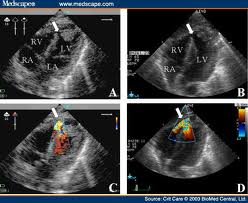

echoEchocardiogram, or simply echo, is a sonogram of the heart. Echocardiography uses standard two-dimensional, three-dimensional, and Doppler ultrasound to create images of the heart. Echocardiography is routinely used in the diagnosis, management, and follow-up of patients with any suspected or known heart diseases. It is one of the most widely used diagnostic tests in cardiology. It can provide plenty of helpful information, including the size and shape of the heart, pumping capacity and the location & extent of any tissue damage.